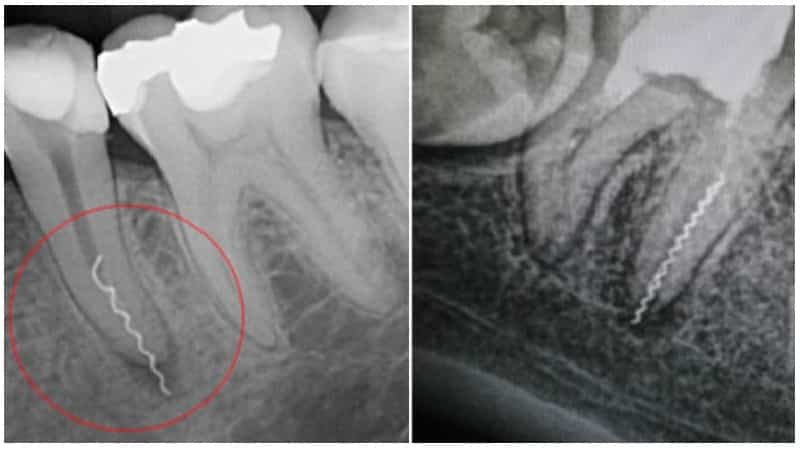

Поломка инструментов в зубной полости.

Неправильное использование стоматологических инструментов, недостаток опыта и несоблюдение технических норм могут привести к поломке (расколу или крошению) инструмента.

Часто мелкие осколки остаются в полости зуба или открытой ране, повреждая мягкие ткани. Это может не быть замечено во время процедуры, но впоследствии может вызвать сильное воспаление, нагноение тканей и даже аллергическую реакцию на металл.